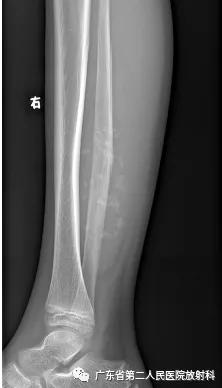

X线正侧位

(1)X线:右侧胫、腓骨中下段后方可见一软组织密度肿块,部分边缘模糊,肿块内可见多发点片状高密度影,边界清楚,胫、腓骨中下段受压向前、外侧移位。